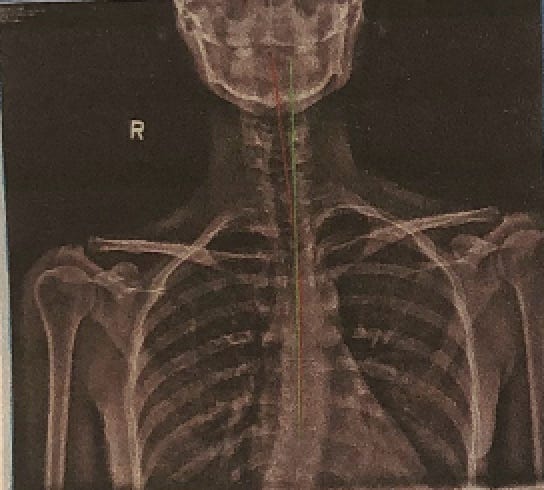

Without staying on top of my genetic imbalances, compensation can happen and happen quickly. Sometimes it’s a tight left hamstring, other times it’s been a tight left piriformis or a tight left calf. Lately it’s been a combination of all three, and it all stems from my scoliosis.

I was diagnosed with idiopathic scoliosis when I was 15 and the highest my curve ever measured was 23°—not terrible considering the degree of curvature that some of my family members have (thanks, Dutch genes! I got the scoliosis without the height.) It wasn’t enough to have me put in a brace nor be a candidate for surgery, and so I was sent to PT to complete endless clam shells.